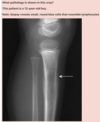

**Answer: Osteosarcoma** ## Footnote Osteosarcomas are malignant osteoid- and bone-forming tumours that arise from mesenchymal stem cells (osteoblasts) located in the periosteum. In this x-ray, the tibial metaphysis shows extensive osteolytic medullary and cortical bone destruction combined with sclerotic bone formation (seen posteriorly in particular). The lesion affects the entire width of the bone, and there are marked periosteal reactions on both margins. On the posterior margin, massive invasion of the surrounding soft tissue can be seen.